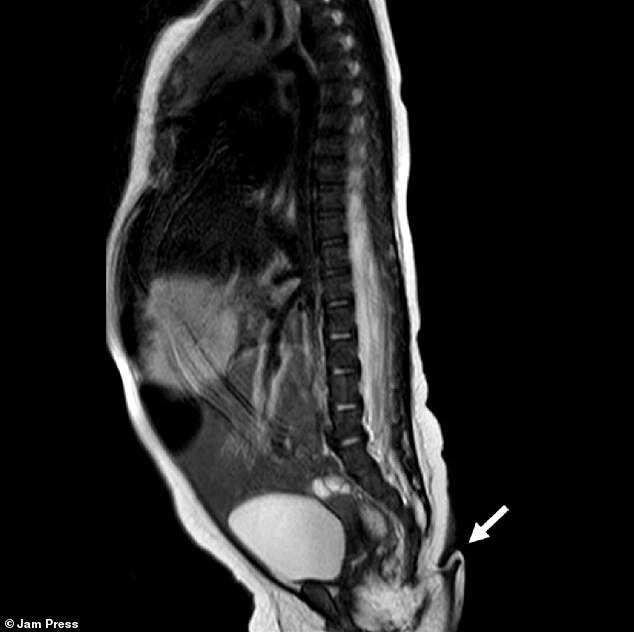

پزشکان میگویند این دختر مکزیکی از نظر سایر اندامها از جمله مغز، قلب، کلیه و حس شنوایی سالم بود. همچنین، اسکنهای پزشکی نشان داد که این دم نتیجه مشکلی در ستون مهرهها مثل دیسرافیسم نبود؛ این بیماری باعث میشود مهرهها بهدرستی شکل نگیرند و در پایین ستون آنها زائدهای شبیه دم رشد پیدا کند.

محققان پس از دو ماه دوباره این نوزاد را بررسی کردند و متوجه شدند که وزن و قد او در شرایط عادی قرار دارد. با این حال، اندازه دم 0.8 سانتیمتر بزرگتر شده بود. پزشکان درنهایت طی یک جراحی کوچک که با بیحسی موضعی انجام شد، این دم را قطع کردند. بررسیهای بیشتر روی این زائده نشان داد که دم این کودک شامل بافتهای نرم، رگ و مجموعهای از اعصاب بوده است.